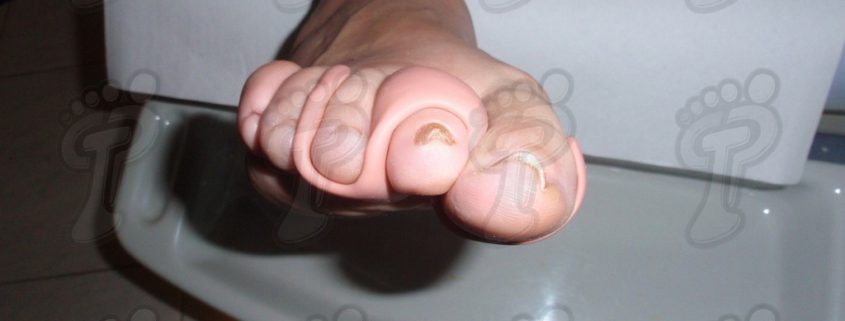

Изготовление силиконового ортеза является полностью ручной работой, и мы должны оценить статику и динамику пациента для достижения терапевтического дизайна. Использование ортезов подходит для пациентов всех возрастов. Может использоваться при лечении различных заболеваний, таких как вальгусная деформации hallux valgus (бурсит большого пальца стопы), когтистые пальцы, клинодактилия, infraductus или supraductus пальцев и т.д. В продолжении я покажу несколько примеров использования ортезов:

Корректирующий ортез в форме Омега для hallux valgus и supaductus второго пальца.Detalle de ortesis en forma de omega.